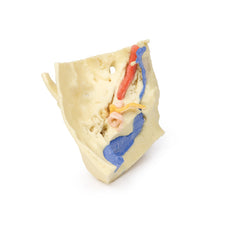

The carotid sheath has been opened on both sides of the neck, and the internal jugular veins and sternocleidomastoid muscles largely removed, to expose the pathway of the common carotid arteries, internal and external carotid arteries, and the vagus nerves. On the right side, the great auricular nerve ascends towards the face, while the hypoglossal nerve can be seen adjacent to the exposed stylohyoid ligament and supra- and infrahyoid muscles. A large thyroid gland is present bilaterally inferior to the thyroid cartilage, with a well-preserved superior thyroid artery and inferior thyroid vein on the right side and across the midline.

The carotid sheath has been opened on both sides of the neck, and the internal jugular veins and sternocleidomastoid muscles largely removed, to expose the pathway of the common carotid arteries, internal and external carotid arteries, and the vagus nerves. On the right side, the great auricular nerve ascends towards the face, while the hypoglossal nerve can be seen adjacent to the exposed stylohyoid ligament and supra- and infrahyoid muscles. A large thyroid gland is present bilaterally inferior to the thyroid cartilage, with a well-preserved superior thyroid artery and inferior thyroid vein on the right side and across the midline.